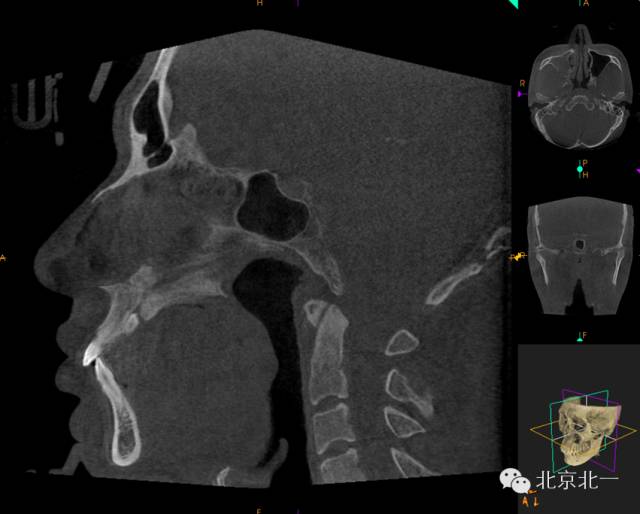

CBCT顯示埋伏多生牙位于腭側(cè)高位,接近切牙管開口位置。

CBCT矢狀位顯示多生牙倒置阻生,位于鼻腭神經(jīng)管口